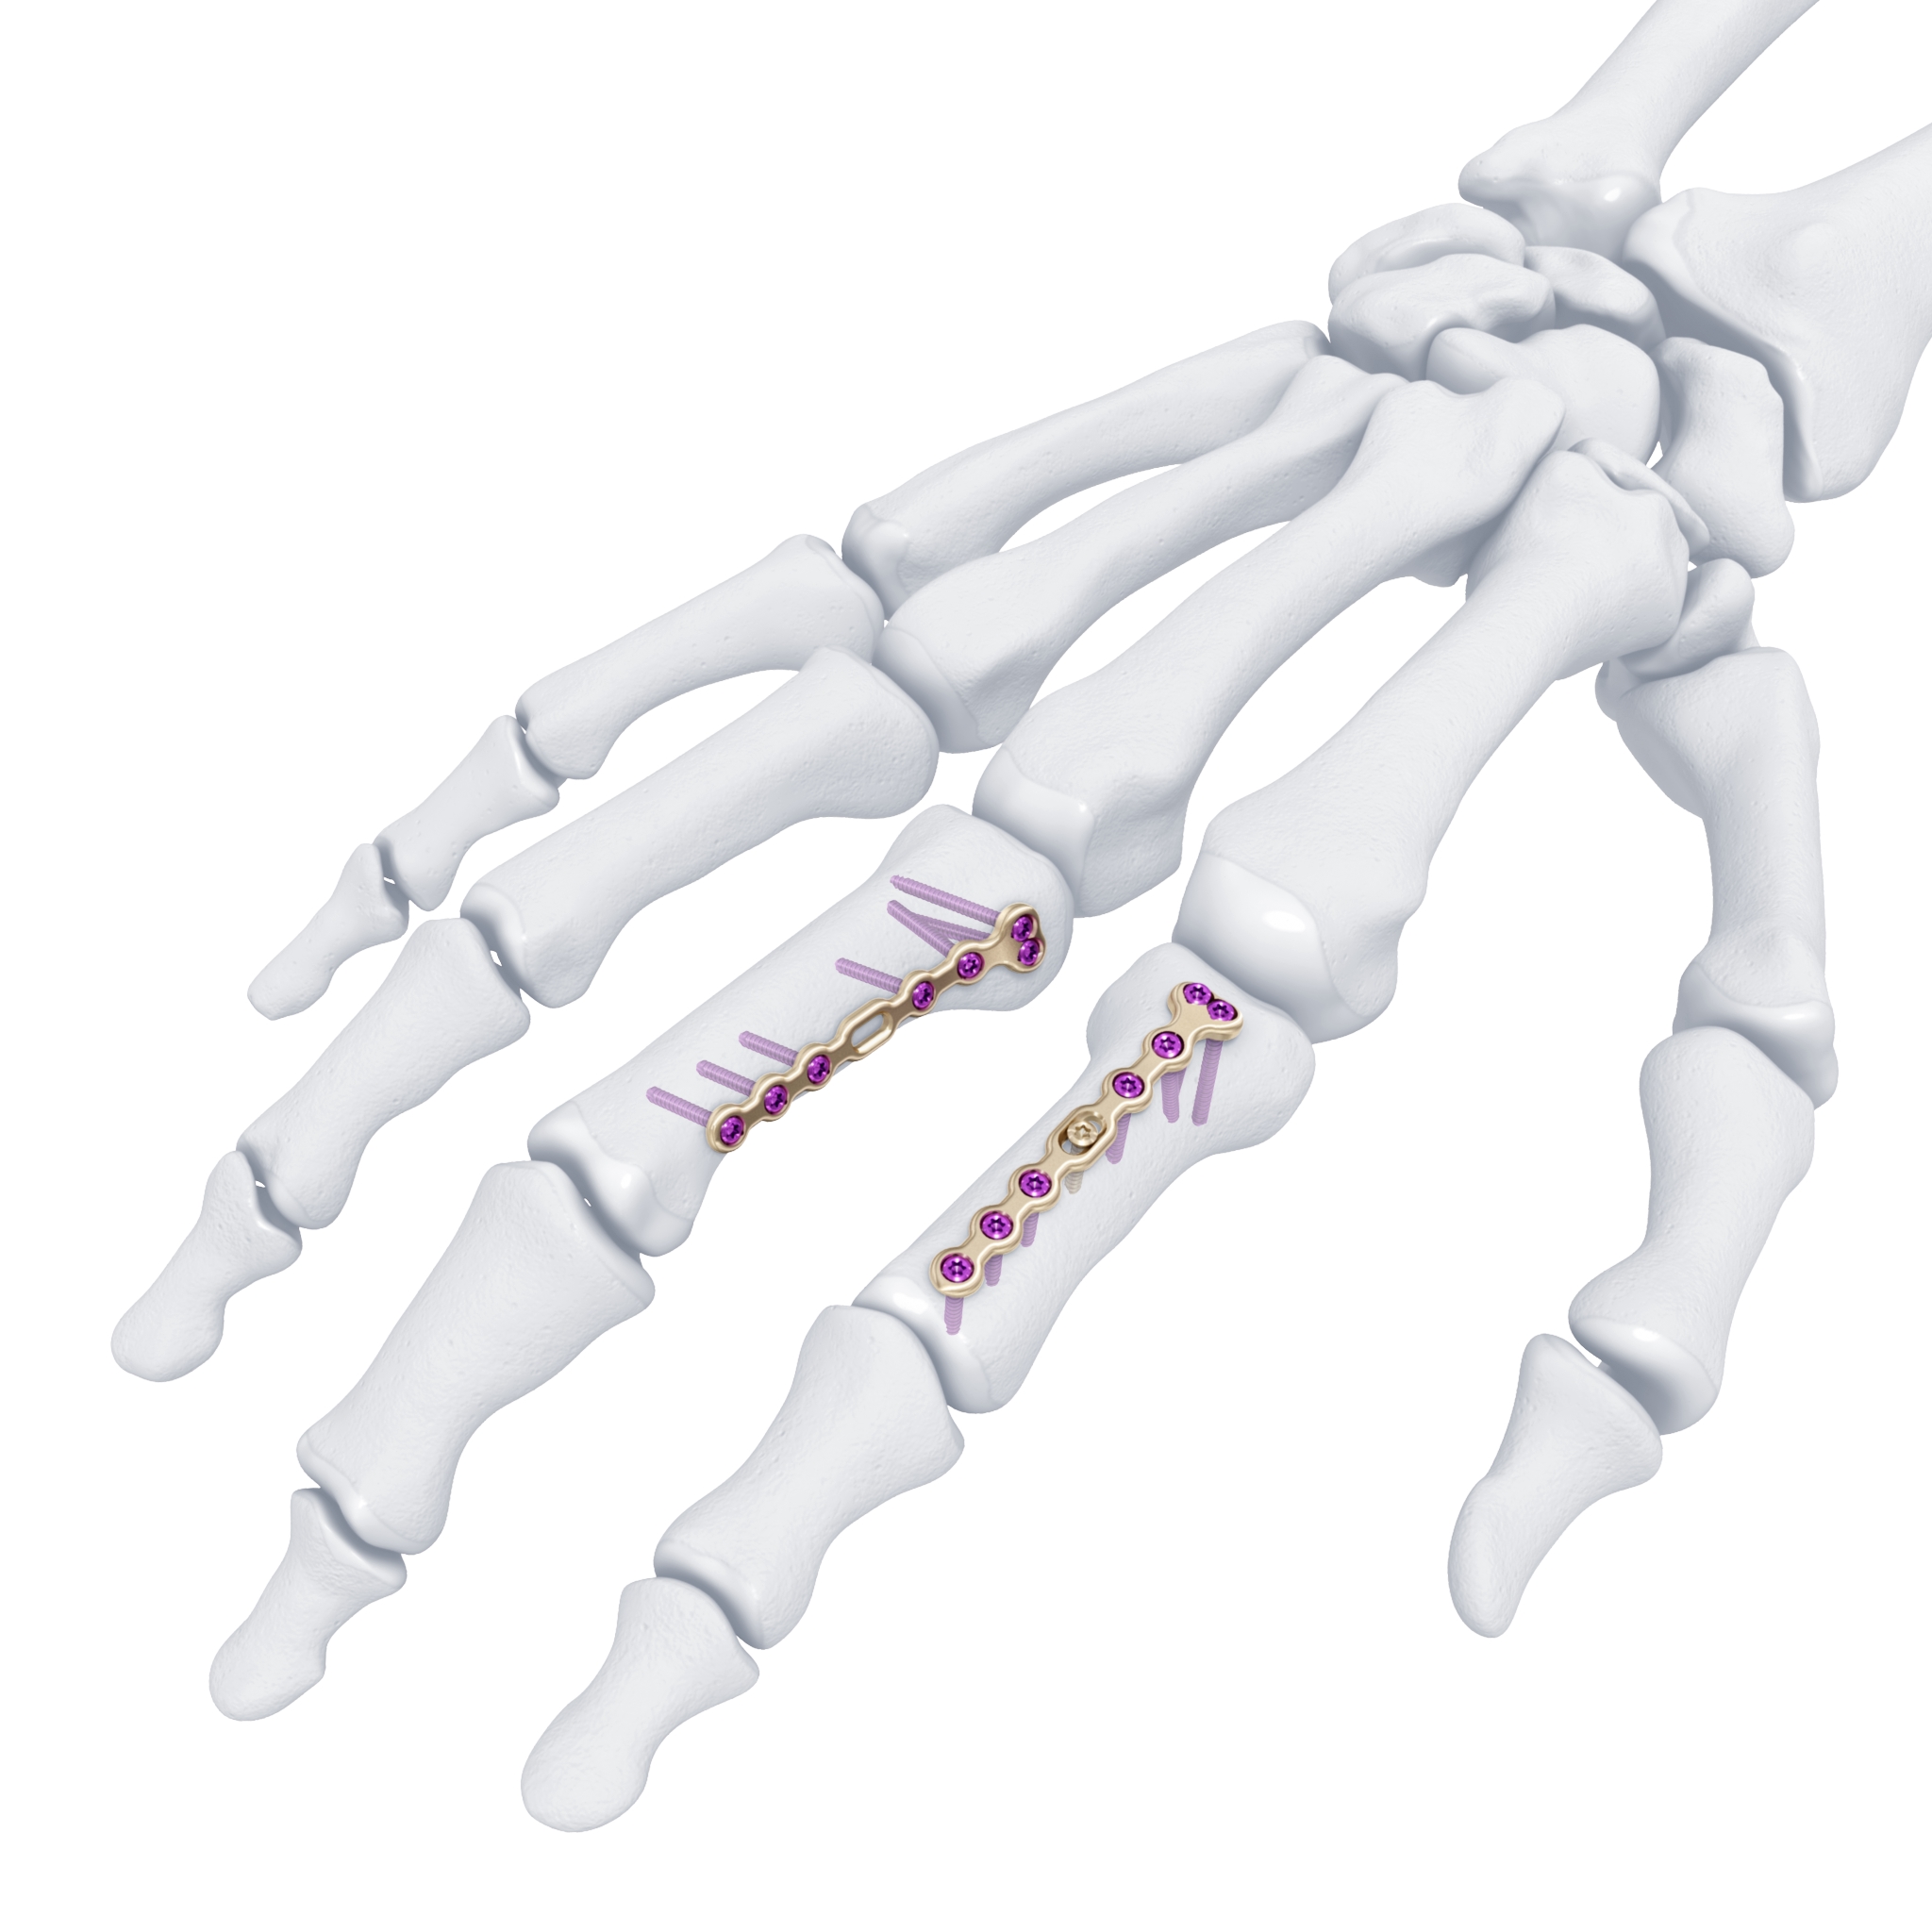

A 20-year-old male suffered a complex multi-digit injury of the right hand requiring revascularization and stabilization of both proximal phalanx and PIP joint fractures (Figs 5 - 8). Multiple plates, including the rotation correction plate from the 1.5 module of the VA Locking Hand System were used for fixation. The Variable Angle Locking system is ideal when only two screws, either proximal or distal, are able to be inserted due to space limitation.

One major advantage of variable angle technology in very distal phalangeal fractures is the ability to be extremely flexible with a wide range of fixation options. Freedom of implant placement assists early mobilization, vital in these complex fractures with associated soft-tissue trauma.